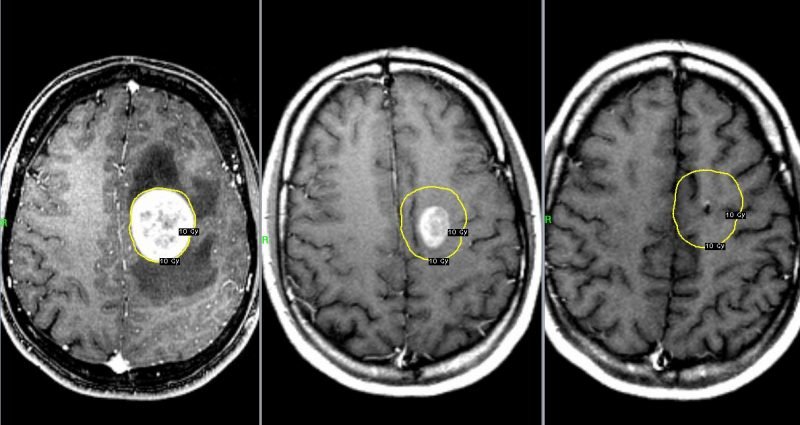

Когда метастазы в структурах мозга

Перемещение метастазов в район головного мозга выявляется в несколько раз чаще, чем их первичное поражение раком. И это неудивительно. Ведь для органа требуется питательных веществ и кислорода намного больше, чем для любой другой части тела. А доставляются они непосредственно с током крови, по которому циркулируют раковые элементы.

Метастазы из молочной железы, тканей прямой кишки или же почек поступают и оседают в ткани мозга на любом этапе ракового поражения. Это, безусловно, серьезный вид осложнения, многократно ухудшающий прогноз для онкобольного.

Диагностировать их помогают современные методики обследования – КТ, МРТ. После чего назначаются комплексные лечебные процедуры. Однако, на их фоне дается лишь несколько продлить жизнь человека. Излечение наступает крайне редко.

У большинства больных, имеющих метастазы в паренхиме мозга, они присутствуют и в иных органах, что также ухудшает клиническую картину.